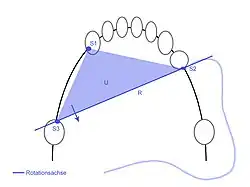

Der Belastungswert der zu ersetzenden Zähne muss nach Vest dem Belastungswert der Pfeilerzähne entsprechen, also mindestens gleich oder größer als dieser sein, um eine ausreichende Langzeitprognose einer anzufertigenden Brücke zu gewährleisten. Fehlen beispielsweise die unteren vier Frontzähne 32–42, die einen Belastungswert von 2 + 1 + 1 + 2 = 6 aufweisen, so genügen die beiden unteren Eckzähne 33 und 43, die einen Belastungswert von 5 + 5 = 10 aufweisen, als Pfeilerzähne zum Ersatz dieser Zähne. Fehlen jedoch die beiden Molaren 26 und 27 (Belastungswert 6 + 6 = 12), so genügen nach Vest die beiden endständigen Zähne 25 und 28 als alleinige Pfeilerzähne nicht (Belastungswert 4 + 4 = 8). Es sollte deshalb der Zahn 24 in einen Brückenzahnersatz mit einbezogen werden (Belastungswert 4 + 4 + 4 = 12).

Retentionsform

Zur Verwertbarkeit eines Zahnes und zu dessen Pfeilerwertigkeit gehört, eine Retentionsform durch Zuschleifen (Präparation) des Zahnes herzustellen. Der Halt einer Krone an einem Zahn wird nicht allein durch das Befestigungsmaterial erreicht. Zusätzlich muss eine leicht konische Form (5°- bis 8°-Konuswinkel) für eine Retention der Zahnkrone sorgen.[29] Ebenso ist die Größe der Retentionsfläche maßgeblich für den Halt einer Krone. Ist ein Zahn zu stark zerstört oder wurde bereits bei einer früheren Präparation zu konisch gestaltet oder ist der Kronenstumpf zu kurz, dann sinkt die Pfeilerwertigkeit erheblich.[30] Es besteht insbesondere im Bereich der Molaren die Gefahr, dass sich die Krone vom Zahn löst. Die Gefahr ist im Unterkiefer besonders groß, da einerseits der Zahnersatz starr ist, andererseits der Unterkieferkörper sich bei der Mundöffnung und bei Belastung verwindet. Die Befestigung der Krone am Zahn muss dieser Kräftedifferenz dauerhaft widerstehen können. Die kontrahierten Musculi pterygoidei laterales (äußere Flügelmuskeln) stauchen den Unterkieferbogen mit der mandibulären Symphyse als Fixpunkt, wodurch sich der Unterkiefer um 0,1 bis 1,0 mm verformen kann.[31]

Bei der Planung einer Brücke oder einer Teilprothese ist die Statik zu ermitteln und welchen Kräften die Pfeilerzähne ausgesetzt sein werden. Die Pfeilerzähne sind dahingehend zu bewerten, ob sie den zu erwartenden Belastungen standhalten können, wobei eine fachgerechte Konstruktion vorausgesetzt wird.[34]